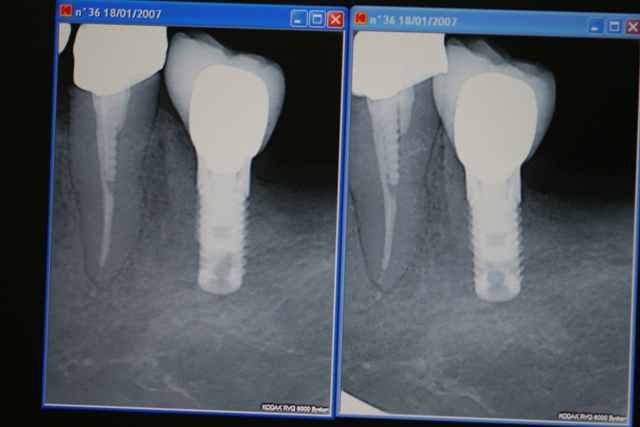

dans le même esprit voila un cas que j'ai réalisé il y à maintenant 5 ans .

mise en place d'un 4*10 en position de 36 lors du forage légère félure de la corticale vestibulaire par blocage du forêt de 2.8

j'ai mis en place l'implant et la suite parle d'elle même...

j'ai alors décidé de le mettre en fonction quand même et au final cinq ans après je n'ai vraiment aucun regret

voici la photo de mon écran , si quelqu'un connait la façon de compresser une rvg issue de kodak en jpeg je suis preneur.

pour répondre à la question précédente je pense que la densité osseuse (typeI+++)n'est pas étrangère au problème dans ce cas précis si tu pense à l'absence de microfiletage du col depuis la macrogéométrie du fût a changé et ça aussi n'est pas étranger au problème et que dire du blocage du forêt...